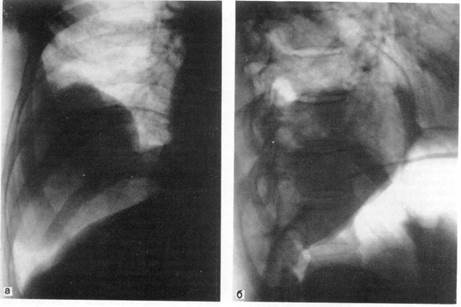

Рис. 3.

Рак верхней доли левого легкого.

а — прямая рентгенограмма: б — боковая рентгенограмма.